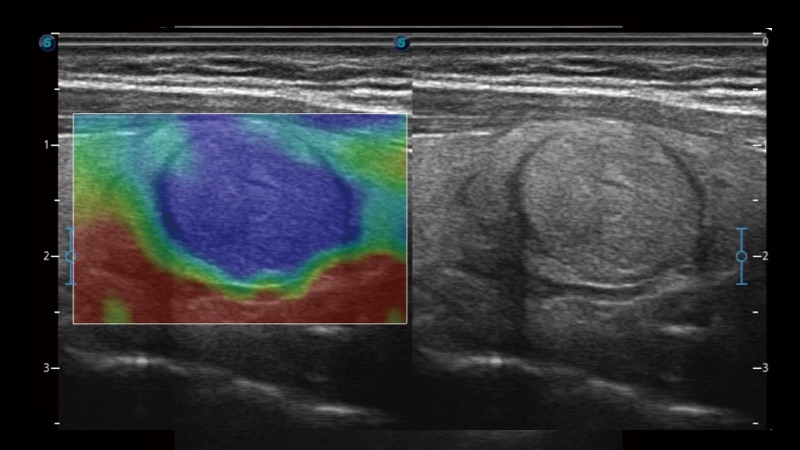

弹性成像

弹性成像无需高频度外力作用可真实反映组织的形变,具有良好的重复性,更早地洞察潜在的病理学特征。